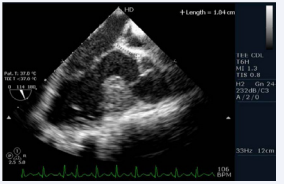

. The echocardiogram showed an elongated left ventricular outflow tract due to subaortic conus (Figure 4, video 5).

Figure 4: Transesophageal echocardiogram long axis view showing presence of subaorticconus with aortomitral discontinuity

There were also sub pulmonary conus with pulmonary tricuspid discontinuity (video 6)

Video 6: Transesophageal echocardiogram long axis view showing subpulmonary conus with pulmonary tricuspid discontinuity

and a small ostium secundum atrial septal defect (left to right shunt). Furthermore, there was thickening of the interventricular septum that appeared as a pouch. The patient underwent cardiac catheterization to define the anatomy and determine the complexity because the VSD was not confirmed. The QP:Qs was 1:1. The left ventriculography revealed a normal contractile ventricle connected to the left sided aorta. There was no evidence of VSD. However, there was opacification of a small pouch just medial to the septum. There was no opacification of the pulmonary artery (Figure 5; video7)